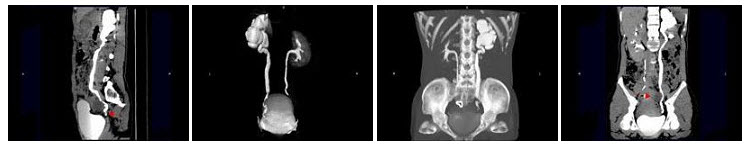

22、多项选择题

女,33岁,右肋腹痛7天,尿检可见大量的脓细胞,CT平扫+增强如图所示,下列说法正确的是()

A.右肾体积增大,其内可见类圆形低密度病灶

B.增强扫描可见该病灶不均匀强化,其内有无强化的坏死灶

C.右肾病灶边界模糊不清

D.考虑为右肾囊肿合并感染

E.考虑为右肾脓肿

23、单项选择题

女,25岁,上腹疼痛不适,低热,有阿米巴痢疾病史,CT检查发现肝右叶低密度病变,如图,最可能的诊断是()

A.原发性肝癌